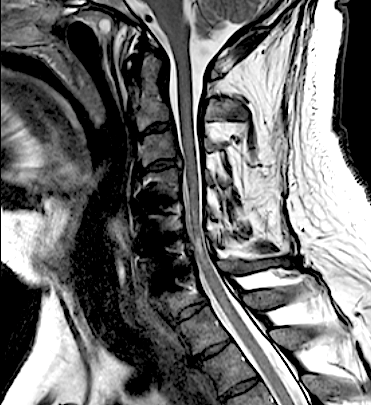

El resultado de la RM cervical planteaba dudas si era necesario o mandatorio realizar una descompresión posterior complementaria. Sin embargo, los parámetros clínicos no sugerían una compresión medular: la evolución lenta a la mejoría de su paresia, la ausencia de progresión de su mielopatía y la ausencia de dolor resultaron determinantes para que se adoptara una actitud conservadora. El paciente fue dado de alta (en plena pandemia de covid) y la evolución fue buena a pesar de que no pudo completar la rehabilitación. Se realizó nueva RM y RX cervical a los seis meses que resultó mucho más concluyente.

A los seis meses de evolución, el paciente sigue pendiente de rehabilitación, ha mejorado su inestabilidad postural y en la marcha aunque persiste la paresia C7 (agravada respecto a preoperatorio, con EMG y registros MNIO con radiculopatía crónica severa).

RM 6 meses

afecta de manera significativa el diámetro del canal vertebral y a la que se realizará seguimiento evolutivo.